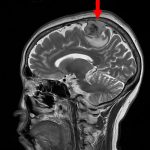

698

'25年11月

40代

右前頭葉腫瘍

頭蓋内腫瘍摘出術

No.’25_100 手術前1

No.’25_100 手術前2

No.’25_100 摘出 前

No.’25_100  摘出 中

No.’25_100 摘出 後